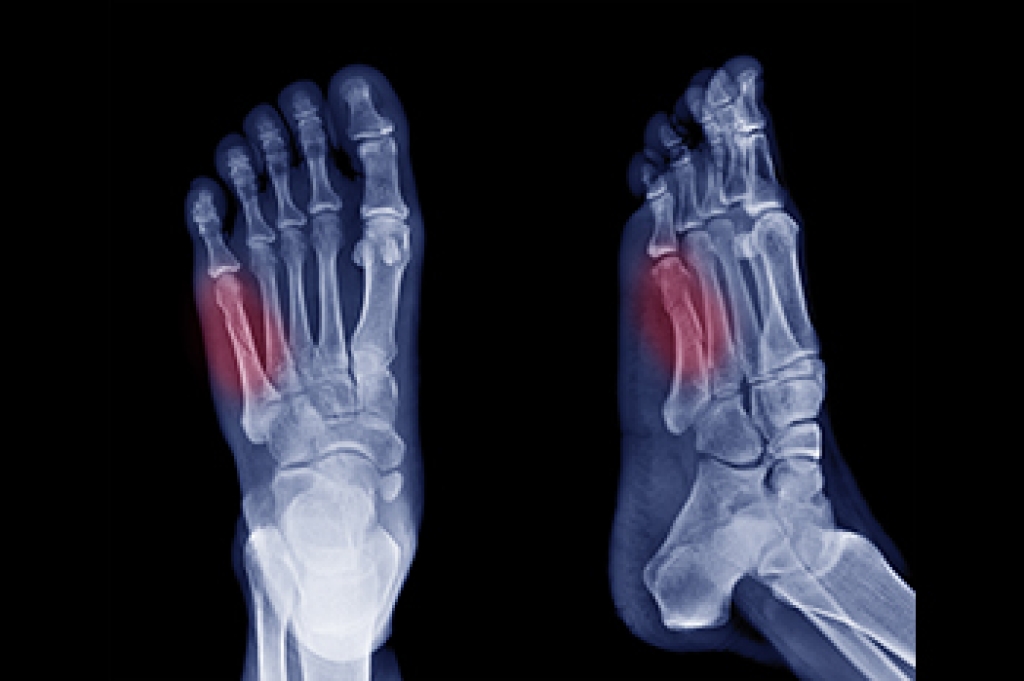

Jones Fracture Symptoms

A Jones fracture refers to a break or crack in the fifth metatarsal bone, located on the outer side of the foot near the ankle. Symptoms typically include pain, swelling, bruising, tenderness on the outer part of the foot, and difficulty walking. Diagnosis usually involves a visit to a podiatrist, who will perform a physical examination, review the symptoms, and take a detailed medical history. To confirm the fracture, imaging tests like X-rays are commonly used. Treatment options depend on the severity of the fracture. For minor cases, rest, mild pain relievers, and possibly a cast or splint may be recommended. Crutches could also be necessary to help avoid putting weight on the affected foot. In more severe cases, surgery may be required to properly heal the bone. Full recovery can take several months, so it is important to allow enough time for the bone to heal completely to prevent further injury. If you suspect you have a Jones fracture, it is suggested that you consult a podiatrist for an accurate diagnosis and personalized treatment plan.